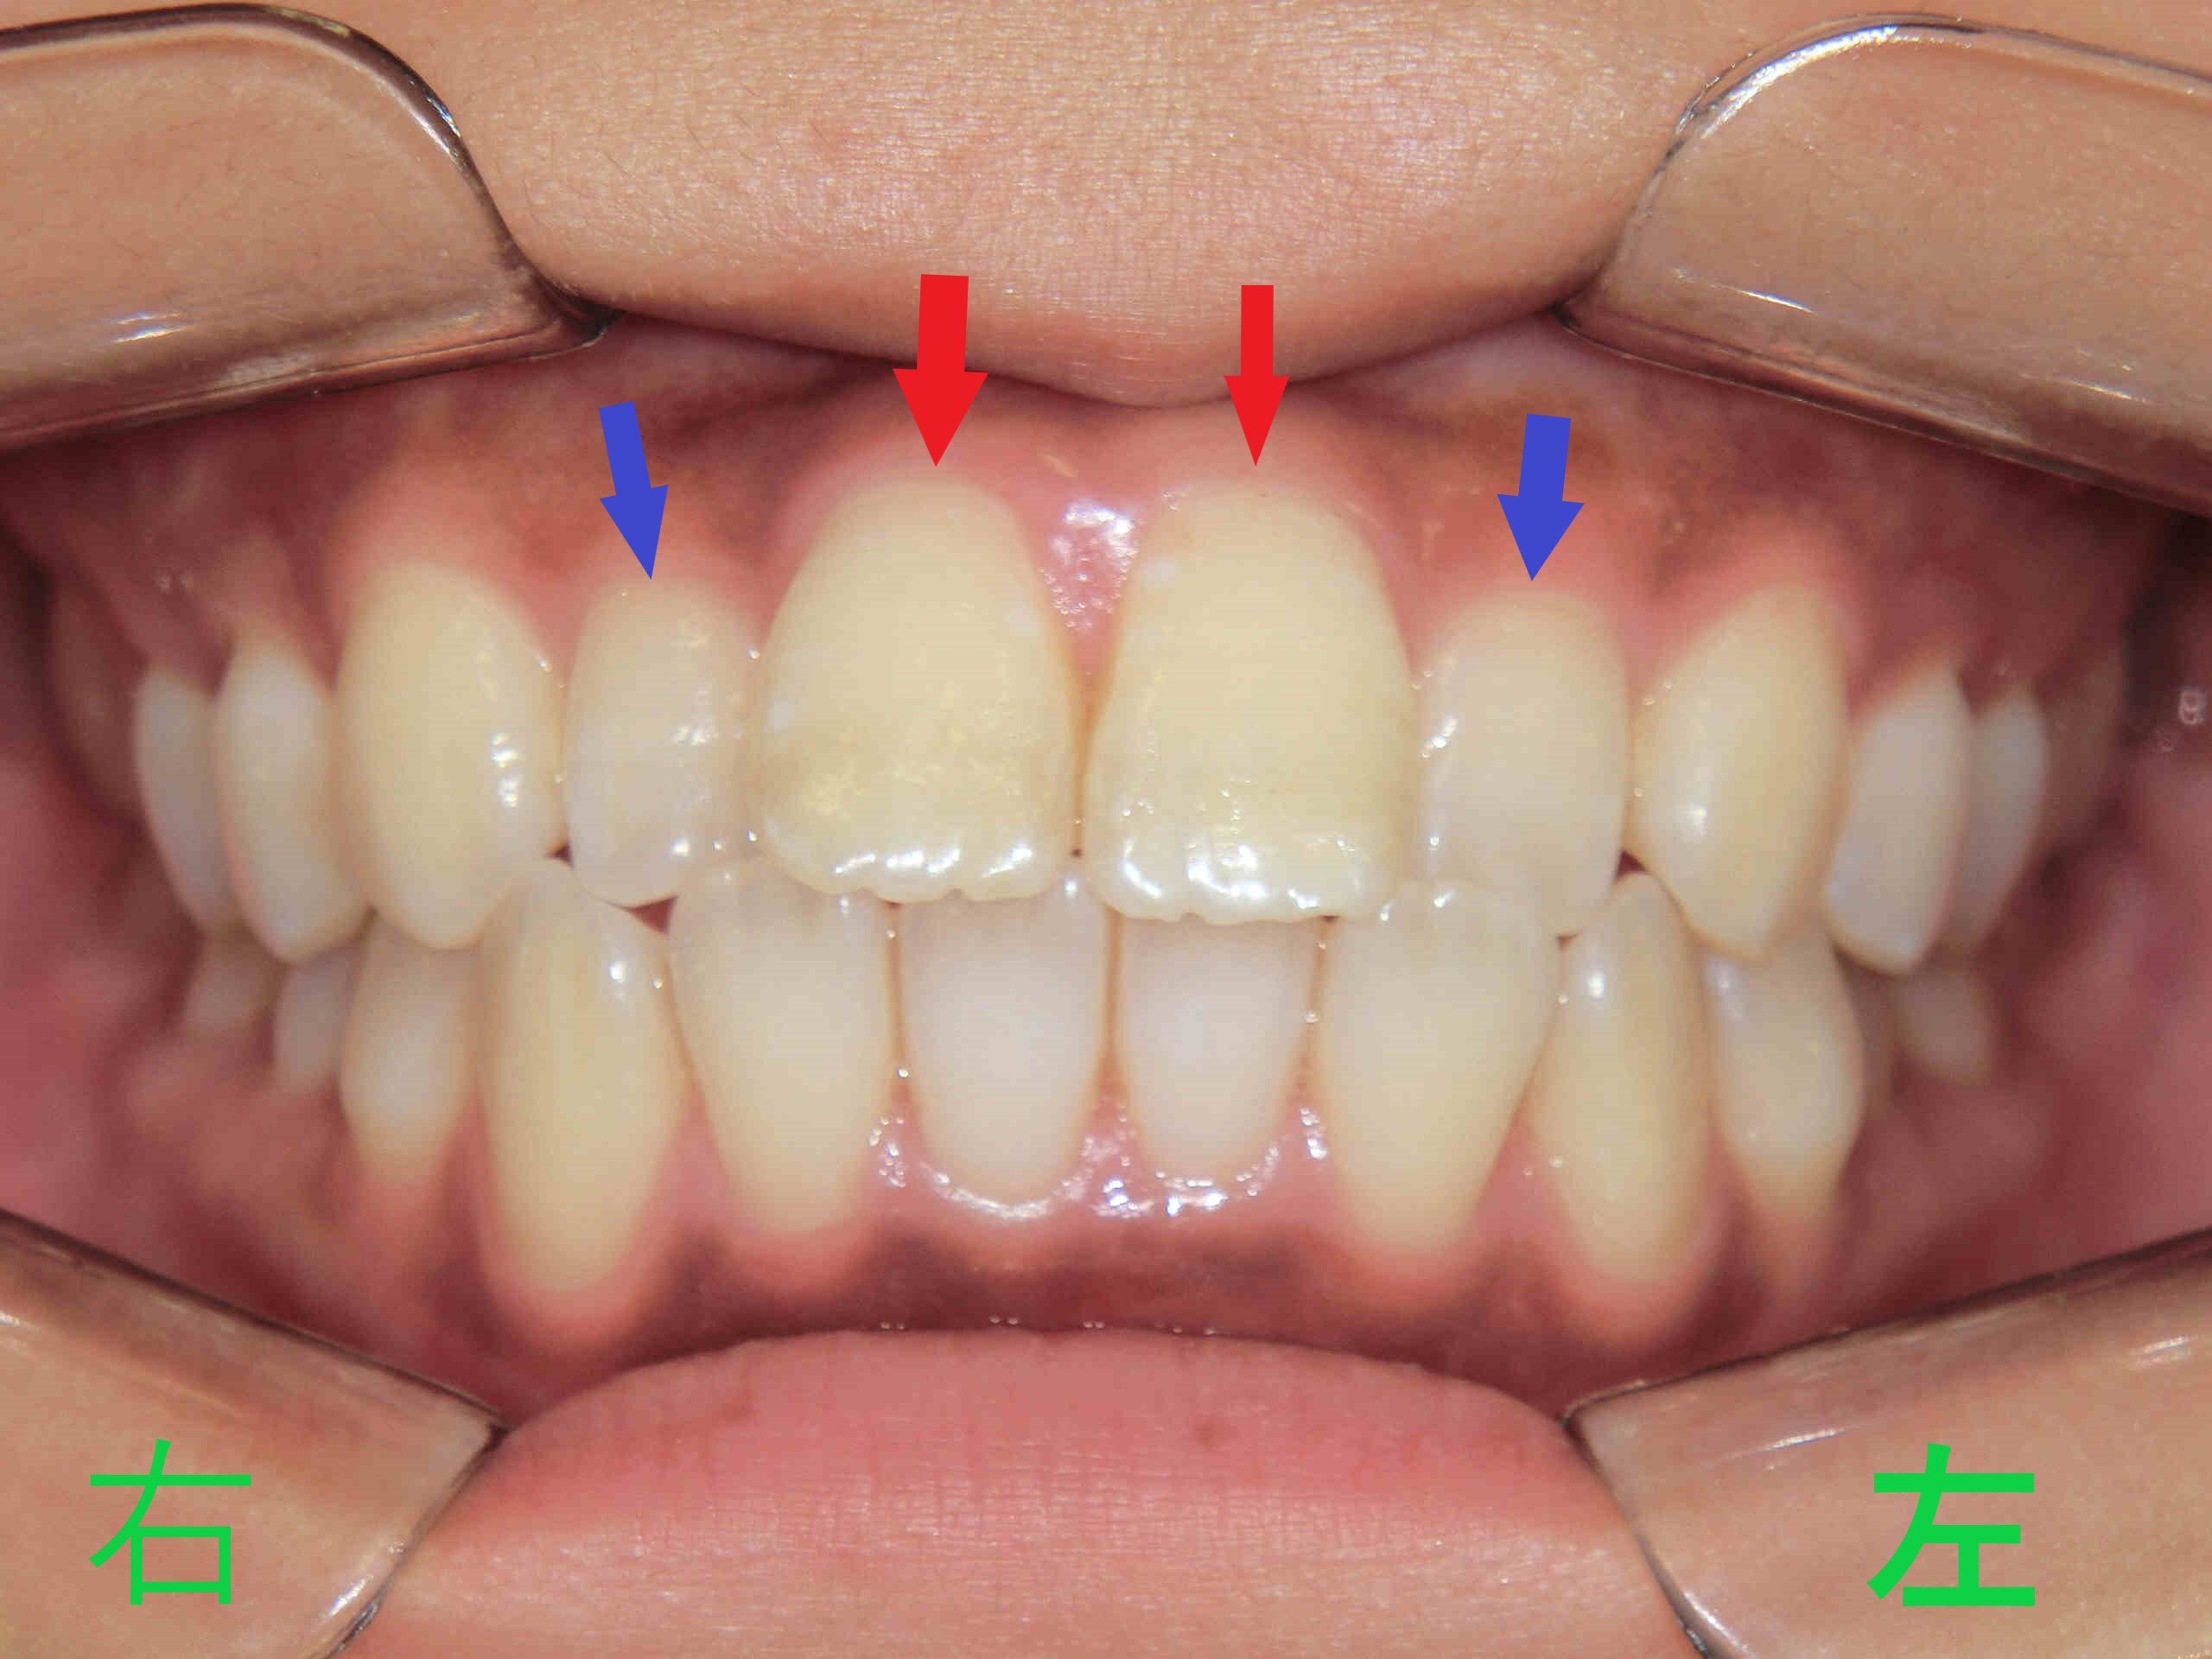

上記写真をご覧ください。

こちらは、みらい歯科・矯正歯科クリニックに勤務する歯科衛生士の口腔内写真で、マウスピース矯正(スマイルトゥルー)による治療前の様子を記録したものです。

患者本人は、以前より上顎左右中切歯(赤色矢印)の前突感(いわゆる出っ歯)と、上顎左右側切歯(青色矢印)の逆被蓋(下顎前歯より内側に位置している状態)を気にされていました。